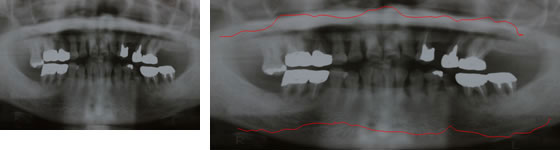

歯周病のレントゲン写真

ほぼ健康な方の骨の状態

ほぼ健常な方の骨の位置です。歯が骨の中に2/3位入っています。

状態:健常な状態

少し歯周病が進行された方の骨の状態

少し歯周病が進行してきた方の骨の位置。歯が骨の中に半分ほどしか入っていません。

状態:軽度(P1)、中度(P2)

重度の歯周病の方の骨の状態

重度に歯周病が進行した方の骨の位置です。歯が骨に1/3以下しか入っていません。

状態:中度(P2)、重度(P3)